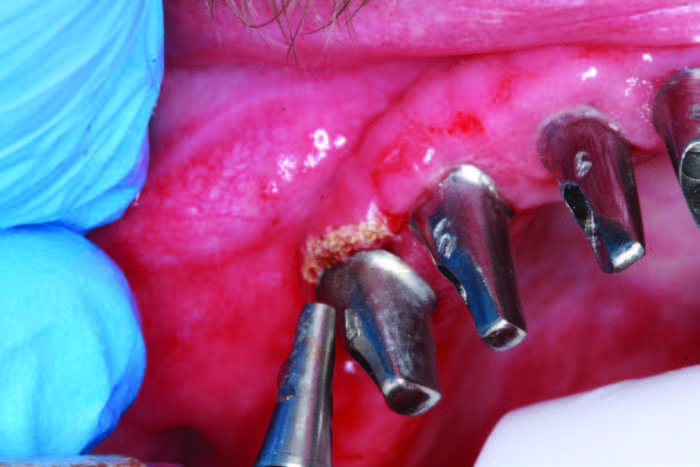

At the time of edentulation, the mandibular implants were placed. The Tapered Internal Implant System (BioHorizons) has Laser-Lok technology, or micro-grooves that allow the implant to be placed subcrestal, equicrestal, or supracrestal to hold on to the bone and hemi-desmosomes of the tissue. The buttress threads provide for aggressive cutting, progressive bone loading, and excellent bone-implant contact, while the 1.5-mm deep internal hex provides a stable seal of prosthetic components. Implant placement was performed according to CBCT analysis. After placement, the lip of bone on the lingual was removed with the Piezosurgery by Mectron. The flat side of BioHorizons’ 3inOne abutment was oriented toward the labial for ease in orientation after uncovering and for impressions where a ball top screw can be used with this abutment as an impression transfer coping (Figure 7). After 4 months of healing and the uncovery of the permucosal healing abutments, the soft tissue was healthy and had great keratinized tissue (Figure 8a). The preliminary impression allowed the lab team (Glidewell Dental Laboratory) to return a verification jig to assess the accuracy of the impression and to ensure that the prosthesis would seat passively. The Sheffield one-screw test was performed after luting the verification jig together with Primatec Pattern Resin (Figures 8b and 8c). This resin has less than 0.1% shrinkage, making it the luting option of choice when compared to other types of luting resins. Once the jig was luted, alternate screws were loosened, and the terminal screws were also loosened to verify the jig would not lift up. A master impression (Aquasil Ultra Xtra [Dentsply Sirona]) was taken over the verification jig. This impression material provides an extended set time of 5 minutes to allow for adequate time to load the tray, inject around abutments, and find the screw access channels using the open tray impression technique.